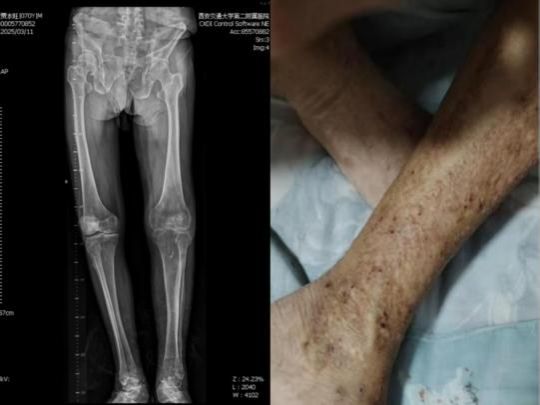

七十岁的山西患者贾伯被轮椅推进诊室时,双膝已扭曲成怪异的“O”型。二十余年骨关节炎的折磨,让这位昔日的“铮铮硬汉”不得不扶着助行器,以厘米为单位挪动脚步。更令人担忧的是因常年神经性皮炎导致全身皮肤瘙痒难耐,布满抓痕的小腿皮肤皲裂如干旱的土地,渗血处结着褐色的痂,像一张无声控诉的病痛地图。

术前患者双下肢全长X线片患者入院时下肢外观照